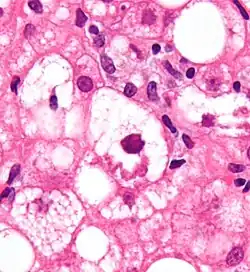

- badanie histopatologiczne:

- stłuszczenie wielkokropelkowe

- obraz plastra miodu

- mitochondria olbrzymie

- ciałka Mallory’ego

- włóknienie

- zmiany zapalno-martwicze